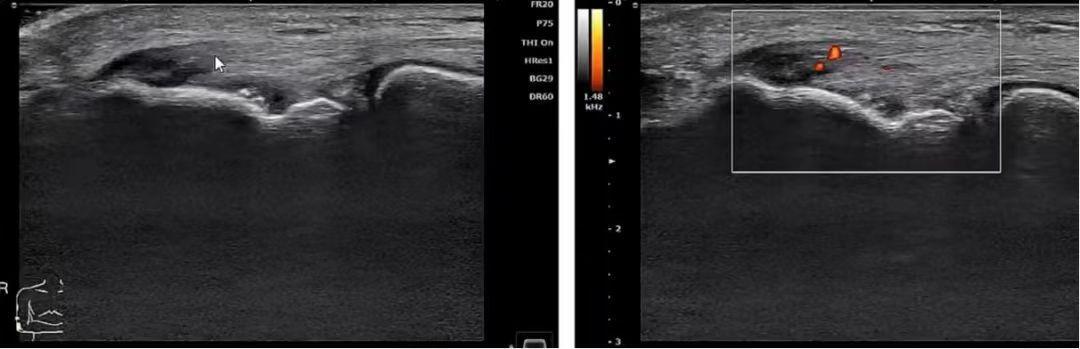

病例1 妈妈肘(网球肘)

妈妈肘,也叫网球肘,又称作肱骨外上髁炎,许多妈妈由于抱小孩或者做家务时,出现急性扭伤或慢性劳损,引起附着于肱骨外上髁处的一些纤维的不全撕裂及骨膜炎性反应,从而出现了这种病症。

▲伸肌总腱肿胀增厚,回声减低。CDFI:急性期可见丰富血流信号,呈“火海征”;慢性期可见少量血流信号